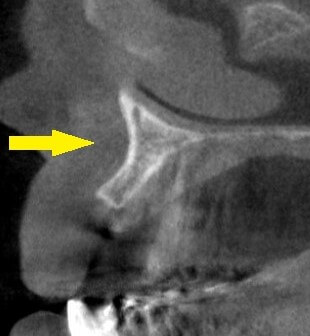

しかし、2本とも骨の幅が薄く(2段目の左右の写真)、通常埋入が困難であったので、インプラントの外側に骨補填材を充填して、骨幅を増やす手術を行いました。

3段目の写真が手術後のCTです。

インプラントの外側に、骨補填材が白く写っています。